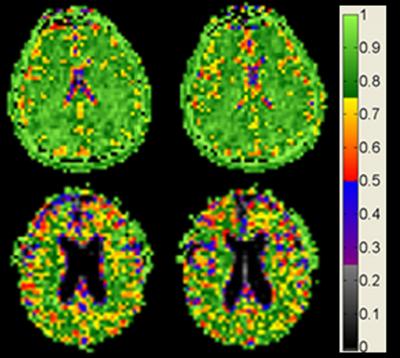

image: Brain cell density remains constant with age among cognitively normal adults. view more

Credit: Courtesy of Dr. Keith Thulborn

The images provide the first evidence that in normal aging, cell density is preserved throughout the brain, not just in specific regions, as previous studies on human brain tissue have shown. The findings also suggest that the maintenance of brain cell density may protect against cognitive impairment as the brain gradually shrinks in normal aging.

The 9.4 Tesla MRI measures sodium ions, which are less concentrated by several orders of magnitude than the fat and water molecules detected with standard MRI. Sodium ions are present throughout the body and are pumped in and out of neurons to generate the electric potentials needed to spark nerve impulses. Sodium concentrations in the brain reflect neuron density. Areas of low sodium concentration indicate lots of neurons packed tightly together, while higher sodium concentration can indicate more space between cells -- or the loss of cells, as in the case of neurodegenerative diseases.